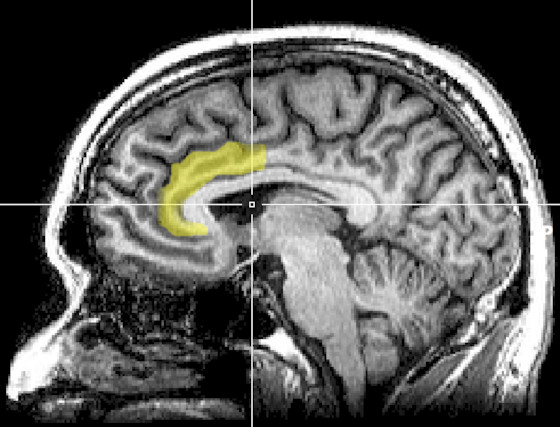

The aMCC is a brain structure that sits in the anterior (or front) medial portion of the brain between the two hemispheres and wraps around the head of the corpus callosum.

The aMCC acts like a control center in the brain, involved in making decisions about what actions are worth our effort in terms of the energy we need to spend versus the rewards we might gain. It’s connected to many parts of the brain, helping it to process information about how our body feels, make plans, and decide what to pay attention to. This makes the aMCC key in preparing us for action and efficiently using our energy to achieve what we want.

The research shows that the aMCC is linked to various behaviours: it’s associated with reduced feelings of not wanting to do anything (apathy), with grit and determination, and with deciding to keep going even when it gets tough. Essentially, it’s involved in weighing the effort required against the potential reward and pushing through challenges.